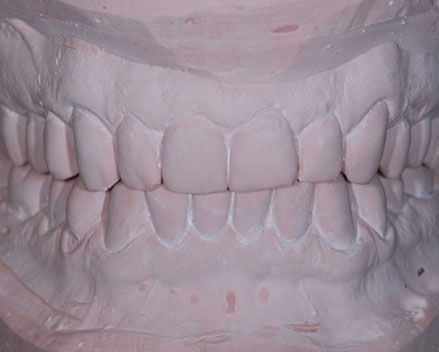

due impronte della bocca da cui si ricaveranno dei modelli in gesso

Nei ragazzi di età superiore (quando la maggior parte dei denti permanenti sono in arcata) e negli adulti, si interviene con trattamenti fissi mirati sia alla risoluzione delle malposizioni dentarie, sia alla correzione degli incongrui rapporti intermascellari in modo da allineare i denti e migliorare l'estetica raggiungendo una buona funzione masticatoria.